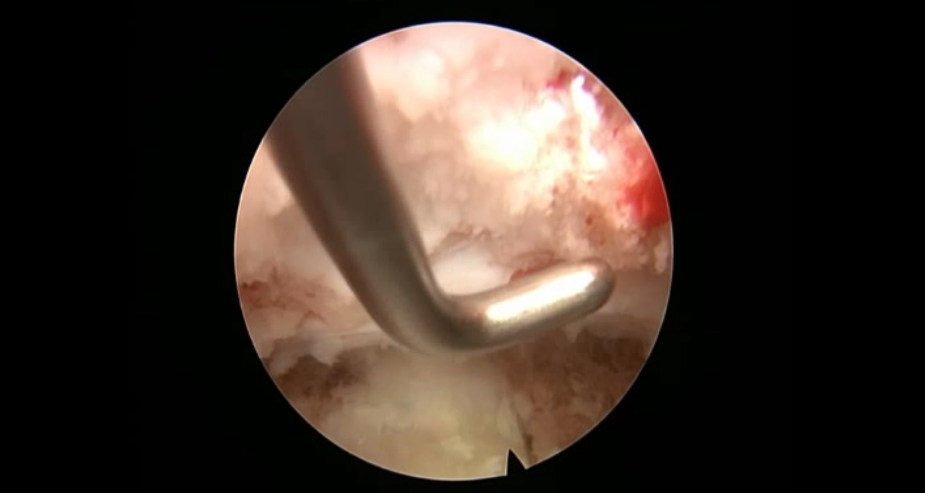

术中资料

点击以上图片,查看术中视频(超链接:http://res.orthonline.com.cn/video/case5---20.mp4)

点击以上图片,查看术中视频(超链接:http://res.orthonline.com.cn/video/case5---30.mp4)